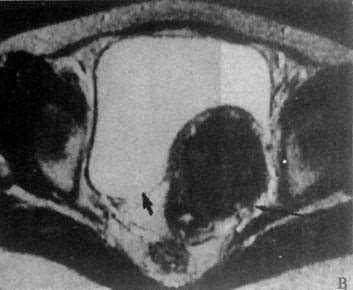

(一)子宫肌瘤CT表现为子宫增大,有时可见肿块向外隆突或呈分叶状。肌瘤密度可等于或低于正常子宫。如出现瘤内钙化则可确诊为子宫肌瘤。子宫肌瘤在T1WI上表现为均匀的中等强度信号,略低于正常子宫肌层,但难以区分;T2WI上则肌瘤信号高于子宫肌层,易于识别。瘤内钙化表现为低信号。坏死区在T1WI上为低信号,T2WI上为高信号(图4-5-7)。

图4-5-7 子宫肌瘤MRI

T1WI横切面,子宫肌瘤表现为中等强度信号,轮廓光滑整齐(↓),压迫膀胱左后壁(↓)

B、T2WI子宫肌瘤信号稍低且不均匀(↓),膀胱内尿液成为极强信号(↓)